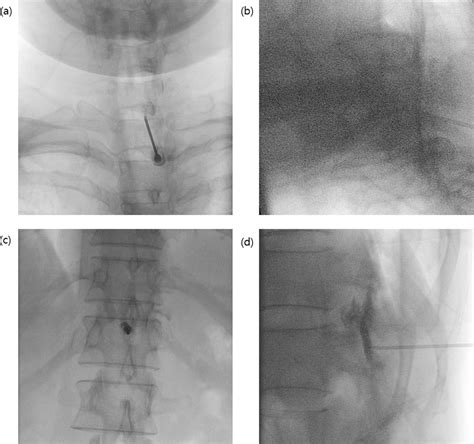

The EBP procedure is typically performed in a sterile environment, such as an operating room or a procedure suite. The steps involved are as follows:

The patient is positioned either sitting or lying on their side, depending on the clinician's preference and the location of the dural puncture. The skin over the injection site is cleaned and draped to maintain sterility. Local anesthesia is administered to numb the area.

A small amount of blood, usually 10-20 mL, is drawn from the patient's vein. This blood will be used for the patch.

The clinician inserts a needle into the epidural space at the level of the dural puncture. The blood is then slowly injected into the epidural space. The needle is removed, and a sterile dressing is applied to the injection site.